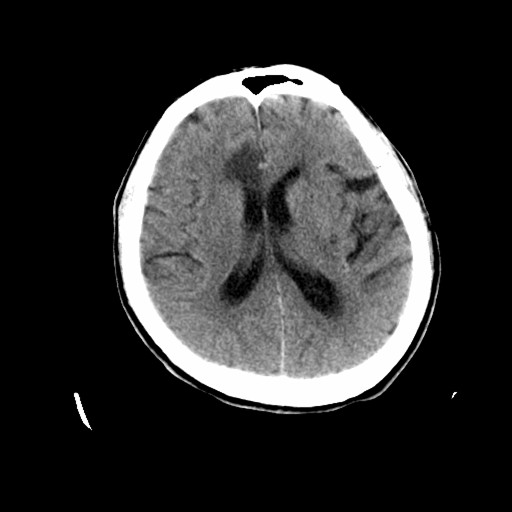

标题: CT19998:男,68岁,突然偏瘫一天 [打印本页]

标题: CT19998:男,68岁,突然偏瘫一天

1天梗塞密度也太低点了吧,不除外占位性病变,建议增强.

分水岭区梗塞

多考虑占位,右侧脑室前角受压。

考虑右侧额顶叶脑梗塞。

支持梗塞表现

好像只能以梗死来解释。